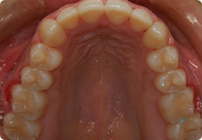

Caso: 12 años

Adolescente: Clase II

Dental Maxilar Protrusion

Extract U4’s/L5’s

4 series de alambres:

.016″, 022″, .0215″ x .028″, .019″ x .025″ Trenzado

Elástico clase 2 2oz. TP amarillos y verdes

Retenedores: Interior Fijo de TMA y Hawley en superior

Tiempo de tratamiento: 15 Visitas